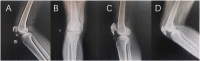

Objective: This study aimed to compare the biomechanical stability and clinical efficacy of the Kirschner-wire (K-wire) tension band combined with patellar cerclage and an anchor-loop plate (ALP) in treating inferior-pole patellar fracture. Methods: The finite element model was established to analyze the mechanical properties of a K-wire tension band combined with patellar cerclage and ALP fixation in the treatment of inferior patellar pole fracture. The clinical data of 49 patients with patellar inferior-pole fracture (AO/OTA 34 A1) admitted to our hospital from January 2017 to July 2021 were retrospectively analyzed. Among these, 28 cases were fixed with ALPs (ALP group) and 21 cases were fixed with K-wire tension bands combined with patellar cerclage (K-wire group). By reviewing the medical records and follow-up results, we compared the operation time, final knee joint activity, incidence of secondary surgery, postoperative complications, and joint function recovery between the two groups. Results: The biomechanical analysis of the finite element model showed that the maximum displacement of the K-wire group was 1.87 times that of the ALP group. The maximum stress of the K-wire group was 1.34 times that of the ALP group. The maximum stress of the pole bone in the K-wire group was 13.89 times that of the ALP group. The average follow-up times of the K-wire group and ALP group were similar (p > 0.05), and the average ages of the two groups were similar (p > 0.05). The operation time of the ALP group was significantly shorter than that of the K-wire group (p < 0.05).The final knee joint activity of the ALP group was significantly greater than that of the K-wire group (p < 0.05). The Bostman patellar fracture function score of the ALP group was significantly better than that of the K-wire group at 3 and 9 months after operation (p < 0.05). Postoperative complications of the two groups included 1 case (3.6%) in the ALP group with internal fixation-stimulation complications and, in the K-wire group, 3 cases (14.3%) with internal fixation stimulation complications and 1 case (4.8%) with infection. Conclusion: The ALP and K-wire tension band combined with patella cerclage models were tested at 500 N, and no damage occurred, indicating that the newly designed ALP is safe in mechanical structure. The ALP has better therapeutic effect in biomechanical stability, postoperative complications, secondary surgery, and knee function. This technique is an effective method for the treatment of inferior-pole patellar fracture.